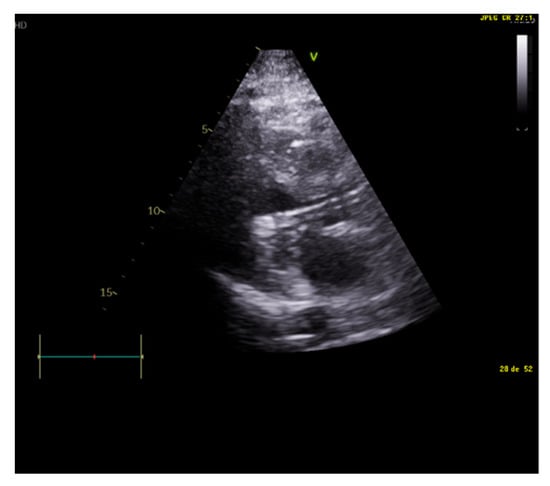

Figure 2.

Restrictive diastolic filling pattern.